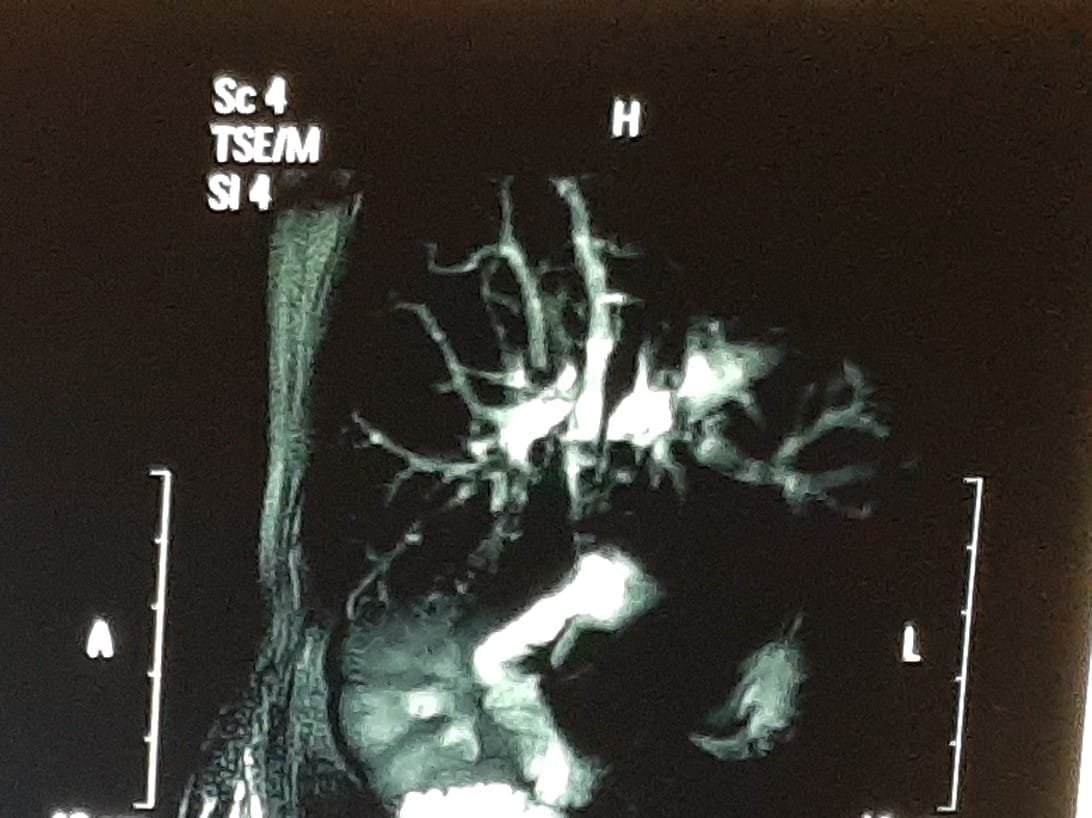

The bile ducts are a series of thin tubes that go from the liver to the small intestine. Their major job is to move bile from the liver and gallbladder into the small intestine, where it helps digest the fats in food. Bile ducts within the liver are called intrahepatic bile ducts. The left and right hepatic ducts exit the liver and join to form the common hepatic duct. Lower down, the gallbladder (a small organ that stores bile) is joined to the common hepatic duct by a small duct called the cystic duct. This combined duct is called the common bile duct. The common bile duct passes through part of the pancreas before it joins with the pancreatic duct and empties into the first part of the small intestine (the duodenum).

Multidetector Ct scan and MRI both usually required for stage the disease and know about surgical curable or not.